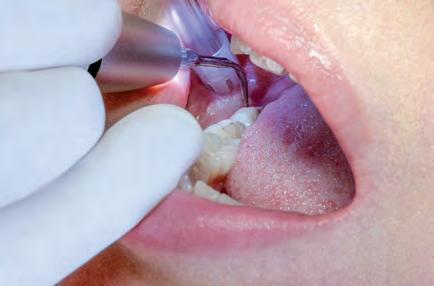

Fokus på bitewing bilden. Röntgen för tandhygienister

Tandhygienistens kompetens innefattar att självständigt undersöka patienter med avseende på karies och parodontit. Det är därför viktigt att förstå betydelsen av detektorplacering, projektion, exponering, eventuell bildbehandling och bildtolkning. Här går vi igenom bitewing bildens betydelse som ett hjälpmedel för ett lyckat resultat och även ökad kunskap om förändringar som kan ses på bilden utöver karies och parodontit.

Arbetskurs i komposit för tandsköterskor och tandhygienister

Är du en tandsköterska eller tandhygienist som vill lära dig göra kompositfyllningar på ett enkelt och kvalitetsmässigt sätt? Då är detta en kurs för dig!